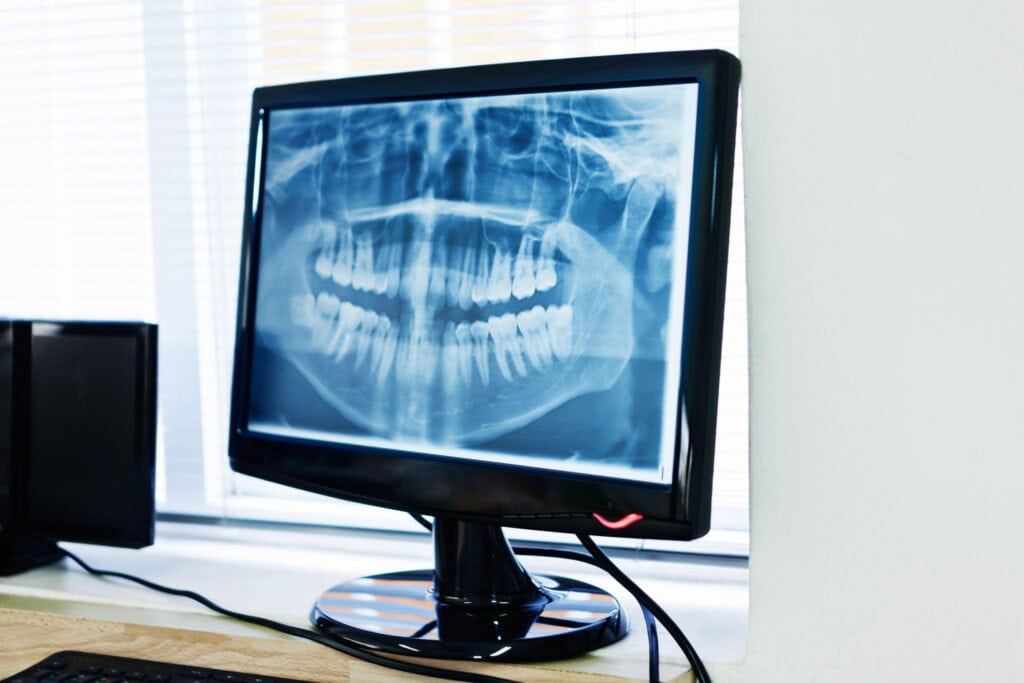

We take lots of dental images for local practices as we have a super duper machine! We currently have two dental nurses undergoing their dental radiography training.